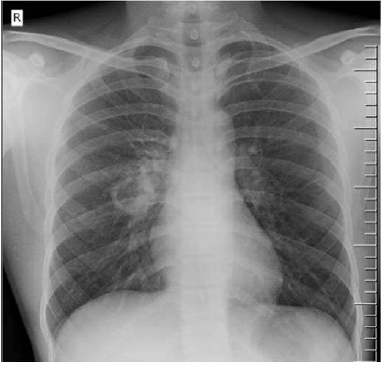

Paciente do sexo feminino, de 39 anos de idade, natural e procedente de São Paulo – SP, sem comorbidades, procura atendimento no Centro de Saúde Escola por quadro de perda ponderal de 8 kg em 4 meses, tosse produtiva, febre baixa no início da noite, fadiga e nodulações cervicais. Ao exame, revela-se emagrecida, descorada 2+/4+, afebril, com nodulações endurecidas em cadeias cervicais anterior e posterior, com ausculta cardíaca sem alterações e estertores crepitantes em ápice direito. Realizou a radiografia de tórax apresentada a seguir.

Internet: <radiopaedia.org>.

Considere que, após confirmação do diagnóstico do quadro pulmonar, a paciente receba o resultado de dois testes rápidos positivos para HIV e, posteriormente, seja realizada carga viral de 10.000 cópias/mL e contagem de linfócitos T CD4+ = 150 células/mL. Nesse caso, em relação ao tratamento do HIV e da patologia pulmonar, deve-se iniciar,

Caso clínico para a questão.

Com base nesse caso clínico, assinale, entre as alternativas a seguir, aquela que apresenta a principal hipótese diagnóstica do quadro pulmonar e seu exame confirmatório, respectivamente.